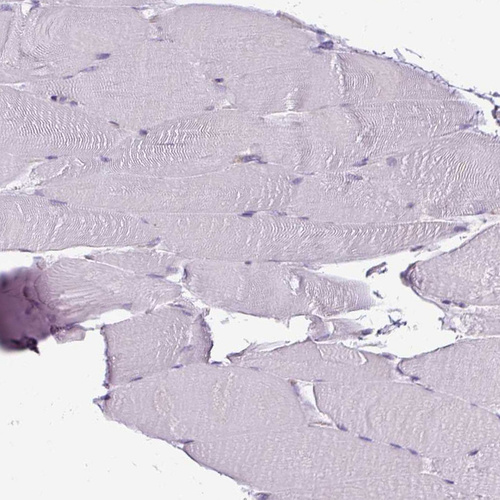

Immunohistochemistry analysis in human tonsil and skeletal muscle tissues using HPA051248 antibody. Corresponding SH3BGRL RNA-seq data are presented for the same tissues.